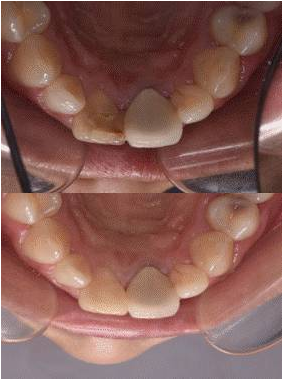

11去除暫封材料,清理髓腔,選擇性釉質(zhì)酸蝕,涂自酸蝕粘結(jié)劑,牙本質(zhì)色樹(shù)脂充填牙本質(zhì)層,牙釉質(zhì)色樹(shù)脂充填釉質(zhì)層,調(diào)牙合修形,拋光。圖10[1]/11/12(停止漂白后,需等待2周以上[2],以使顏色穩(wěn)定、氧氣消散及恢復(fù)粘結(jié)力,若患者時(shí)間緊迫,為了中和過(guò)氧化物的氧化性,也可用過(guò)氧化氫酶沖洗髓腔,或應(yīng)用氫氧化鈣覆蓋髓腔2天)

圖11 治療后唇側(cè)觀

圖12 治療后舌側(cè)觀

圖13 治療前后唇面對(duì)比

圖14 治療前后舌側(cè)對(duì)比